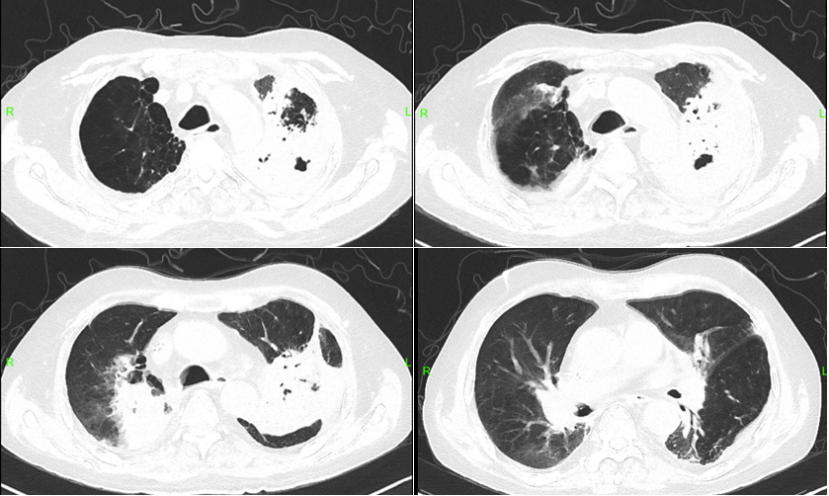

202310月9日,复查胸部CT:左肺感染并膨胀不全较前进展(图7)利奈唑胺600 mg q12h静滴+ SMZ 2片tid口服+伏立康唑150 mg q12h口服。调整治疗后,患者症状逐步好转。

7  复查胸部CT(2023-10-09)

20231116日,随访胸部CT:右肺门占位并阻塞性炎症,大致同前;左肺感染并膨胀不全,较前病灶范围缩小;肺气肿、多发肺大疱形成,同前;双肺多发慢性炎性病变,部分间质性改变,大致同前(图8)

8  复查胸部CT(2023-11-16)